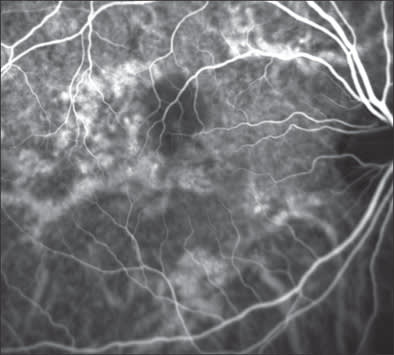

Figure 2A. Late-phase angiogram showing filling of pigment epithelium detachment in chronic CSR.

Fluorescein angiography often documents pinpoint areas of hyperflourescence in central serous retinopathy (CSR) and clearly both FFA and OCT show the resulting pigment epithelial detachments (Figures 2A and 2B). However, ICGA documents marked choroidal hyperpermeability that persists even after the fluorescein leakage resolves. Figure 2C demonstrates the marked engorgement and leakage of the choroidal vessels along with their correlation to the retinal vessels in this same patient and Figure 2D (a widefield mid-phase cSLO ICG image) demonstrates that this choroidal hyperpermeability exists throughout the choroidal circulation and is multifocal, existing even outside the arcades. Patients with hyperpermeable choroidal vessels often have frequent and severe CSR recurrences and may possibly be predisposed to the development of polypoidal choroidal vasculopathy (PCV).